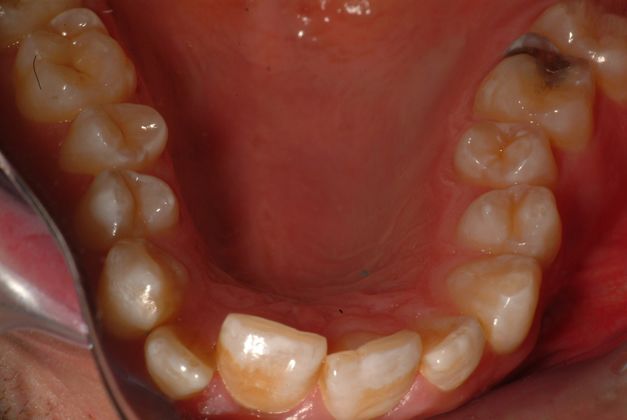

Invisalign Before & After

If you have healthy teeth and gums and wish to correct mild to moderate misalignment, you are likely a good candidate for orthodontics with aligners. Invisalign can correct:

- Crooked teeth

- Gaps between teeth

- Protruding upper teeth

- Overlapping or crowded teeth

- Overbites, underbites, crossbites, or open bites